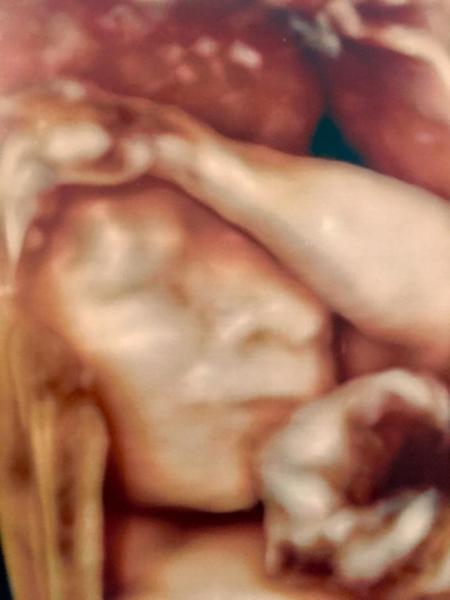

Hallo ihr Lieben, wir sind zurück von der Feindiagnostik! Alles ist gut! :) Endlich haben wir auch ein Outing!!! Es wird ein ........... MÄDCHEN! Darf ich vorstellen: Little Miss Sophie:

Bild zu Zurück von der Feindiagnostik mit Outing! 💗 - Forum für August - Mamis